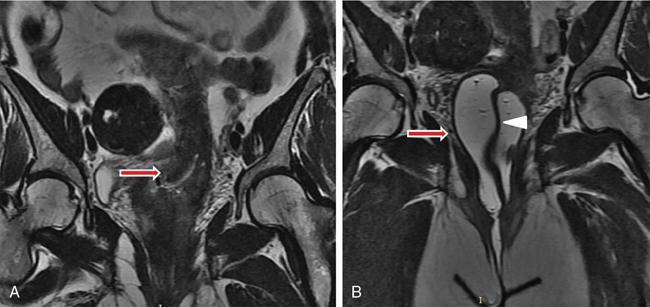

MÜLLERIAN DUCT ANOMALIES Rajani Gorantla Müllerian ducts are a pair of tubular structures that give rise to uterus, cervix, fallopian tubes and upper two-thirds of vagina. Disruption or failure of normal development can result in occurrence of Müllerian duct anomalies (MDAs). These are commonly associated with other congenital anomalies of urinary tract and ovaries due to the close relationship between the development of mesonephric and paramesonephric ducts; few patients also have associated skeletal system anomalies. The prevalence of MDAs in an unselected population was 5.5%; 8% among the infertile women, 12.3% in women with a history of recurrent pregnancy loss and 24.5% in women with miscarriage and infertility. Most of the patients with MDAs are asymptomatic and found incidentally on imaging for any other gynaecological problems, in evaluation of a patient with renal, skeletal or abdominal wall abnormalities. In symptomatic women, complains are related to the type, severity, obstructive anomaly or nonobstructive anomaly. The symptoms can be obstetric or gynaecological related, includes recurrent spontaneous abortions, infertility, preterm labour, intrauterine growth restriction and abnormal foetal lie. Few adolescent girls may present with primary amenorrhoea, hypomenorrhoea, abnormal vaginal bleeding, cyclical pain and mass. Rarely they can present with pelvic inflammatory disease with abnormal vaginal discharge, dyspareunia and urinary tract infections. The female reproductive system develops from a pair of Müllerian or paramesonephric ducts, urogenital sinus and vaginal plate. The ovaries develop separately from the primordial ridge. It is of great importance to understand the normal stages of development, as failure or interruption of any of these stages can lead to a simple to complex spectrum of anomalies. The three stages of Müllerian duct development include: At 6–10 weeks of gestation age, two paired Müllerian ducts and Wolffian ducts formation occurs. When Y chromosome factor (testicular determining factor) is absent, the Wolffian ducts undergo degeneration. The Müllerian ducts further elongate caudally and cross the Wolffian ducts to fuse in the midline. At 10–13 weeks of gestation age, caudal and lateral fusion of the two Müllerian ducts forms primitive uterovaginal canal, which is possessed of solid tissue initially located side by side and further internal canalization leads to the formation of two channels/canals divided by a septum. At this stage, there is reabsorption of the caudal septum and forms single cervical canal and vagina lumen. In around 15–20 weeks of gestation age, complete resorption of the septum takes place in a caudocranial direction from the isthmus to fundus and development of single endometrial cavity results. The fused caudal part of Müllerian ducts gives rise to the uterus, cervix and upper two-thirds of vagina; the unfused cranial part forms the fallopian tubes (Fig. 11.14.1.1). The lower vagina develops from the urogenital sinus, which is separated from the rectum by urorectal septum around 7 weeks of gestation age. The primitive uterovaginal canal embeds into the dorsal wall of urogenital sinus and forms Muller’s tubercle. Around 13 weeks of gestation, two solid masses known as sinovaginal bulbs originate from the upper part of the Muller’s tubercle, further proliferate into the caudal end of the uterovaginal canal to become a solid vaginal plate. Later canalization or degeneration of the central cells of the vaginal plate forms the lower vagina, which is usually completed by 20 weeks’ gestation. The vertical fusion of the upper and lower vagina occurs with resorption of tissue in between and forms single vaginal cavity (Fig. 11.14.1.2). The vaginal lumen is separated from the urogenital sinus by the hymenal membrane. Just before birth, the hymen normally ruptures due to retrogression of the central epithelial cells. However, a thin fold of mucous membrane persists around the vaginal introitus. The ovaries develop separately from migration of primordial germ cells to the genital ridge. Ureteric buds develop separately and concurrently. So renal anomalies are most commonly associated with MDAs with an association of 30%–50%. Various classification systems have been proposed over the past several decades to describe MDAs. Ideally, same classification system needs to be followed by a gynaecologist, surgeon and radiologist for better communication. Buttram and Gibbons classification was suggested in 1979, and it was based upon the level of failure in normal development and segregate the anomalies into groups with similar clinical manifestations, treatment, and prognosis for foetal salvage. According to Buttram and Gibbons, the uterine anomalies were classified into six classes as described in Table 11.14.1.1. The drawback is the lack of classification of vaginal and other anomalies separately. The ASRM (previously the American Fertility Society – AFS) classification system is the most widely accepted classification worldwide over the past years and was introduced in 1988. According to this classification, MDAs are classified into seven classes (class I to class VII) as mentioned in Table 11.14.1.2. However, several limitations have been described by Grimbizis and Campo in 2010 (Fig. 11.14.1.3). The drawbacks of the ASRM classification system are as follows: Hence in 2016, an updated classification of uterine septum, that is ASRM-2016 was proposed and officially approved morphometric criteria are given for distinguishing between septate, normal/arcuate and bicornuate uteri (Table 11.14.1.3). The VCUAM classification was proposed in the year 2005. The main concern is to provide a simple, systematic, clinical classification in addition to providing a precise reflection of the entire malformation. The female genital organs were divided into the following subgroups in accordance with the anatomy: vagina (V), cervix (C), uterus (U) and adnexa (A). Associated malformations were assigned to a subgroup (M) relative to each specific organ. The disadvantage is due to its inherent complexity, and more than 56,700 individual combinations of anomalies are possible. ESHRE and ESGE established a common working group named CONgenital UTerine Anomalies (CONUTA) in order to devise an improved classification system (Table 11.14.1.4). It was published in 2013. Anatomy is the basis for systemic categorization of the MDAs. The subclasses are divided by the different degrees of uterine deformity and their clinical significance (Fig. 11.14.1.4). Cervical and vaginal anomalies are classified into independent supplementary subclasses (Figs. 11.14.1.5–11.14.1.6). For most of the clinicians, it helped as starting point for the development of guidelines for their diagnosis and treatment. The malformations are graded according to severity, U0–U5, C0–C4 and V0–V4, with U5, C4 and V4 being more severe. Class U3 incorporates bicorporeal fusion defects (didelphys and bicornuate) as this was considered as a more functional mode of classification. Arcuate uterus was not included separately, but this is categorized under normal variant into class U1c. Recent studies have demonstrated that the ESHRE/ESGE system provides an effective and comprehensive classification for almost all the currently known MDAs and overcomes the limits of previous classifications. However, there is a relative overdiagnosis of septate uterus with the application of ESHRE–ESGE criteria has been reported and which potentially might lead to unnecessary surgical overtreatment. C0 C1 C2 Normal cervix Septate cervix Double ‘normal’ cervix C3 C4 Unilateral cervical aplasia Cervical aplasia U4 V0 V1 V2 V3 Normal vagina Longitudinal nonobstructing vaginal septum Longitudinal obstructing vaginal septum Transverse vaginal septum and/or imperforate hymen V4 Vaginal aplasia C MDAs’ characterization and classification is of great significance, as the treatment is determined by the type and severity of abnormality. The various imaging modalities available include: HSG was the most recognized imaging modality, earlier to the development of the ultrasonography (USG) and MRI. It is an invasive fluoroscopic-guided procedure for uterine and tubal assessment, and is performed during the midproliferative phase of the cycle, ideally between days 7 and 10 of the cycle when endometrium is thin. Fluoroscopic spot images obtained to evaluate uterine configuration, uterine filling defects and fallopian tube patency. HSG allows evaluation of only the component of the uterine cavity that communicates with the cervix. The anatomic information about myometrium and external fundal contour will not be provided by HSG. The diagnostic criteria used to diagnose MDAs on HSG include: HSG findings of different MDAs are described in Table 11.14.1.5 and Fig. 11.14.1.10. Virtual HSG is a noninvasive technique performed by using a computed tomography (CT) scanner, done 45 s after the contrast material instillation begins. Contraindications are similar to those for HSG and include pregnancy and active pelvic infection. There is no necessity for retraction of the uterus or manipulation of the cervix. The procedure is quick, easy and prophylactic administration of antibiotics is not required. The use of a power injector helps to ensure a steady low pressure of instillation. The procedure is less painful, more comfortable and easily tolerated by patients than conventional HSG. Radiation exposure sometimes requires cervical clamping, which may result in complications such as bleeding and infection. Transabdominal pelvic ultrasound can diagnose uterine anomalies with accuracy rate of 47%. Two-dimensional transvaginal ultrasound (TVUS) has high sensitivity and specificity than transabdominal study and provided some information about external and internal fundal contours. The detection rate is high if the scan is performed in secretory phase due to better visualization of endometrium. Three-dimensional USG shows great accuracy than 2D USG in evaluation of the uterine morphology. The technique of 3D USG varies with different vendors. It displays both the external and internal fundal contours and lower uterine segment by acquisition of single coronal view of uterus (c-view) (Fig. 11.14.1.11). The only disadvantage is that it is transvaginal study and shall not be done in paediatric age group and sexually inactive women. Three-dimensional TVUS has become the first line of screening tool in most of the infertility clinics as it is noninvasive, faster, repeatable, allows storage of volume data and has multiplanar capability for systematic evaluation of the uterine and cervical cavities. The salient features of various Müllerian anomalies on 3D USG are described in Table 11.14.1.6 with images. Three-dimensional ultrasound is combined with sonosalpingography in this technique and provides better delineation of the uterine morphology. It is a less invasive procedure done in proliferative phase with instillation of saline into the uterine cavity and assessment of the uterus will be done. MRI is a universally accepted imaging modality in the documentation of MDAs and accuracy rate of 100% have been reported. MRI provides excellent delineation of both the internal and external uterine anatomies. T2-weighted (T2W) images are the mainstay of pelvic imaging and are performed without fat suppression. T1-weighted (T1W) images are mainly for the haemorrhagic content. The disadvantages of MRI include time-consuming procedure, not cost-effective, large body habitus, pacemakers, recent surgical history and claustrophobia. The current and proposed MRI protocol given by the European Society of Urology (ESUR-MRI protocol) intends a dedicated evaluation of MDAs as mentioned below (Fig. 11.14.1.12): Vaginal anomalies can be accurately diagnosed with the prior administration of the ultrasound gel, to distend vagina (Fig. 11.14.1.13). It will help in better diagnosis of complex vaginal anomalies, like vaginal septations or vaginal duplication. The normal MRI appearance of uterocervical canal and vagina are shown in Fig. 11.14.1.14. Uterine aplasia/hypoplasia/agenesis is class 1 MDA according to ASRM classification and U5 uterine anomaly according to ESHRE classification. It is a formation defect of the paramesonephric ducts with complete or segmental agenesis of uterus and vagina. The incidence rate is around 10%–15% of all MDAs and considered as the most severe form of uterine anomaly. Most of them have complete uterovaginal agenesis with no single completely developed uterine cavity and are associated with Mayer–Rokitansky–Küster–Hauser syndrome (MRKHS). Two types of this syndrome are depicted. The typical form or type A represents the absence or remnants of the uterus, cervix, upper two-thirds of vagina with normal ovaries and fallopian tube (Fig. 11.14.1.15). The atypical form or type B is associated with the abnormalities of the ovaries, fallopian tubes and genitourinary system (Fig. 11.14.1.16). In a few cases (approximately 10%), unilateral or bilateral uterine remnants and with or without endometrial cavity will be seen (Fig. 11.14.1.17). Most of them present with primary amenorrhoea due to complete uterovaginal agenesis and manifest as MRKHS. These patients have normal secondary sexual characteristics due to the preserved normal ovarian function and phenotype. If uterine remnants with functional cavity is present, will present with cyclical pain along with amenorrhoea due to cryptomenorrhoea and haematometra. USG is the first modality for identification of these anomalies, absence of uterus with normal ovaries is diagnostic. But, it is difficult to locate the uterine remnants and cavity due to small acoustic window. MRI is the gold standard and it classifies into uterovaginal agenesis and hypoplasia. If hypoplasia is identified, sagittal and axial sections are taken. These remnants are seen as T2 hypointense tubular structures, located in close relation to ovaries in the adnexa. Once we identify the uterine remnants, it is important to look for the functional endometrial cavity. These will have reduced endometrial and myometrial width. MRI can easily delineate the zonal anatomy due to its high soft tissue contrast resolution. The management of Müllerian agenesis consists of counselling for the patient and her parents. Some patients with MRKHS opt for creation of neovagina for normal sexual life. Various techniques are available. In the presence of a functional Müllerian remnant, regardless of whether it is communicating or not, medical suppression of menses can be initiated and should be followed by laparoscopic removal of the hypoplastic remnant. Unicornuate uterus or hemiuterus is defined as the unilateral uterine development and the contralateral Müllerian duct could be either partially formed or absent. It is a formation defect and the necessity to classify it in a different class than that of uterine agenesis, which is also a formation defect, is due to the existence of a fully developed functional uterine hemicavity. It is considered as class II anomaly according to ASRM classification and class U4 according to ESHRE classification. The frequency rate is around 20% of MDAs. Renal anomalies most often occur in association with unicornuate uterus and usually on the same side of uterine agenesis. Further unicornuate uterus is divided into two subclasses depending on the presence or absence of a functional rudimentary cavity in ESHRE classification: In ASRM classification, unicornuate uterus is divided into four subcategories: Mostly asymptomatic and presence of the noncommunicating uterine remnants will be identified at the time of infertility work up or caesarean section. If a functional cavity is present, the presentation is dysmenorrhoea or haematometra in an adolescent. The common obstetrics-related complications include abnormal foetal lie, intrauterine growth retardation, preterm delivery, placental abnormalities and uterine rupture. Gynaecological complications are ectopic pregnancy and endometriosis due to retrograde menstruation. On imaging, unicornuate uterus is seen as tubular and fusiform or banana-shaped structure at paramedian location, the endometrium is narrow and tapers to the apex with normal myometrial anatomy and reduced uterine volume. The rudimentary cavity or remnants are better depicted on 3D USG (Fig. 11.14.1.18) and MRI. However, MRI is superior to USG due to its high soft tissue resolution. The rudimentary cavity can communicate with main cavity or connected by fibrous band. The nonfunctioning cavity will be seen as T2 hypointense structure with loss of zonal anatomy (Figs 11.14.1.19 and 11.14.1.20), whereas the functioning cavity will show the deformed zonal anatomy (Fig. 11.14.1.21), and its complications like haematometra as T1/T2 hyperintense endometrial collection. Unicornuate uterus without rudimentary cavity does not require any procedure. But in the presence of communicating or noncommunicating rudimentary horn, surgical resection must be considered to prevent complications. Uterine didelphys is a class III MDA based on the ASRM classification and class U3b bicorporeal uterus according to ESHRE classification with an incidence rate of 5% among the uterine anomalies. It is a lateral fusion defect; results from complete failure of the Müllerian duct fusion. Two noncommunicating endometrial cavities with preserved zonal anatomy are seen with separate cervix. According to ESHRE classification, it is defined as external fundal indentation completely dividing the uterine corpus up to the level of external cervical os. It is most commonly associated with longitudinal vaginal septum in around 75% of cases. Some patients may show transverse vaginal septum and these will be obstructive or nonobstructive type. Renal anomalies are also commonly associated with uterine didelphys. Uterine didelphys is usually asymptomatic and diagnosed incidentally on pelvic examination or caesarean section. The uterine didelphys with obstructed vagina (Fig. 11.14.1.22) will present at adolescence as dysmenorrhoea, haematometrocolpos and haematosalpinx. Sometimes retrograde menstrual flow can cause endometriosis and pelvic adhesions. Obstetric-related complications include abortion/foetal growth restriction and poor pregnancy outcome. The uterine didelphys with obstructed hemivagina due to transverse vaginal septum and associated ipsilateral renal agenesis are the manifestations of the syndrome called obstructed hemivagina and ipsilateral renal agenesis anomaly/Herlyn–Werner–Wunderlich (HWW) syndrome (Fig. 11.14.1.23).